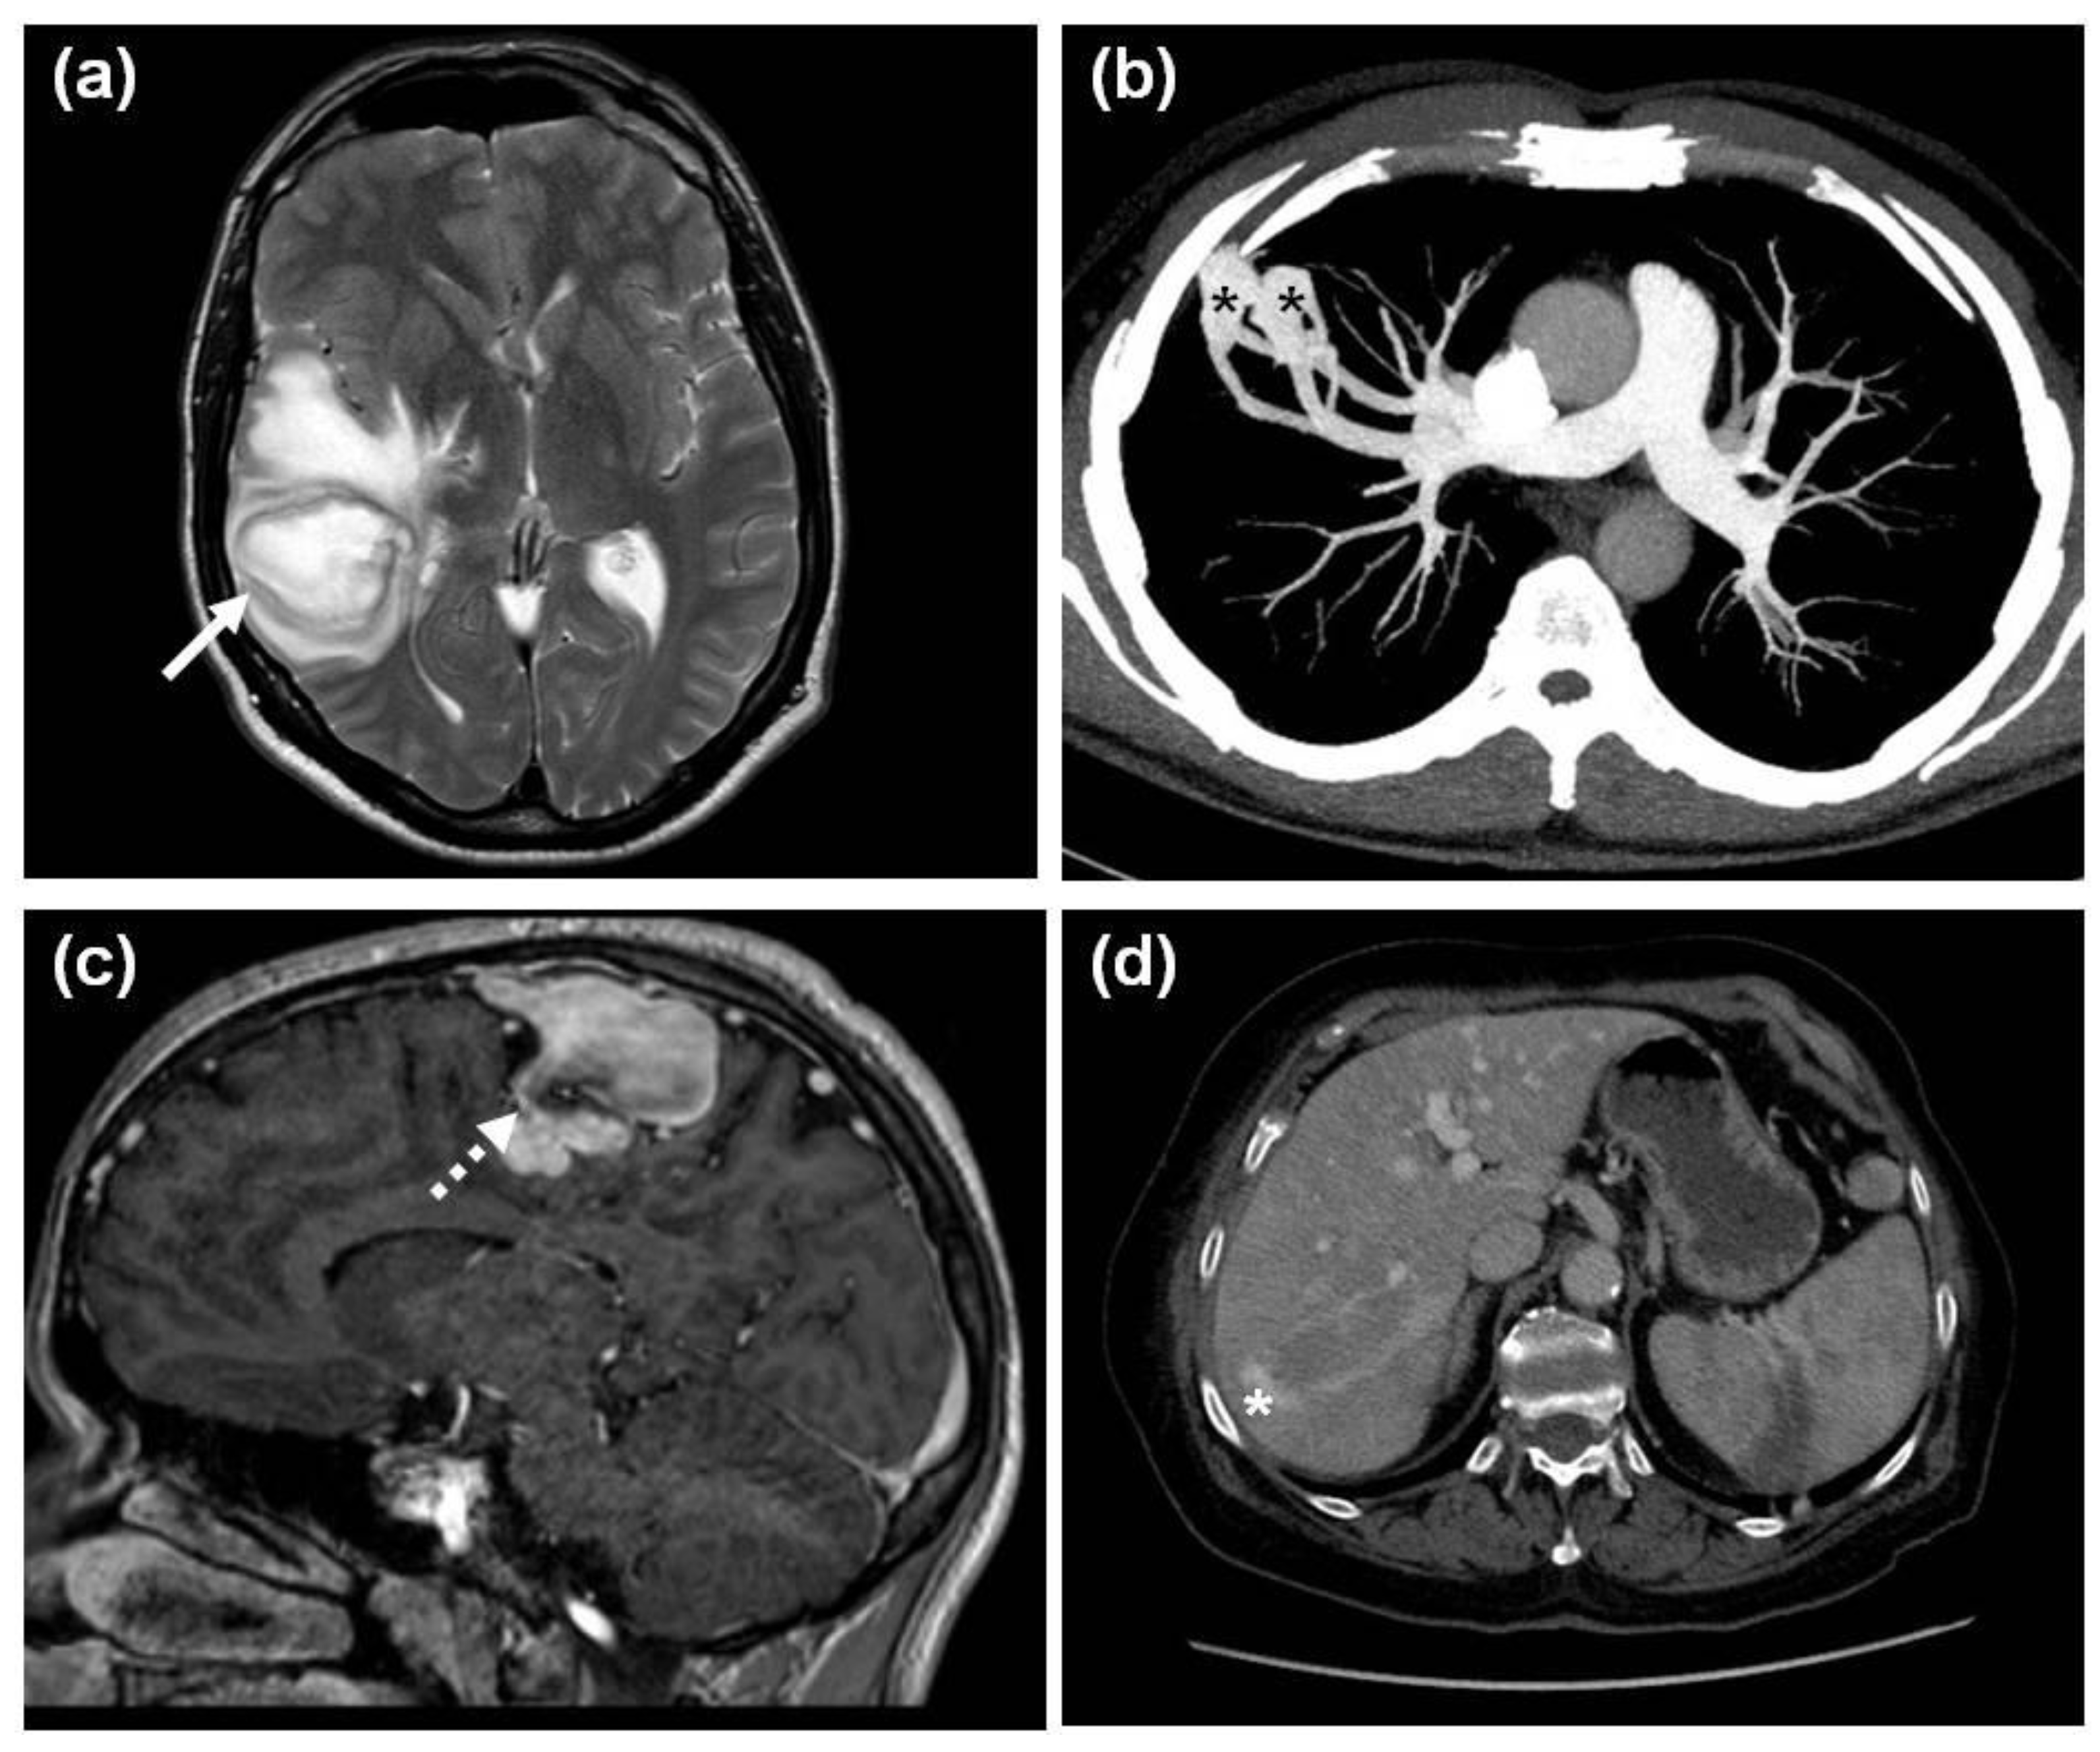

- Major, T.; Csobay-Novák, C.; Gindele, R.; Szabó, Z.; Bora, L.; Jóni, N.; Rácz, T.; Karosi, T.; Bereczky, Z. Pitfalls of delaying the diagnosis of hereditary haemorrhagic telangiectasia. J. Int. Med. Res. 2020, 48, 300060519860971. [Google Scholar] [CrossRef]